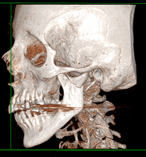

Pseudoaneurysm of the internal maxillary artery secondary to subcondylar fracture: case report and literature review

Alessandro Moro and others

Journal of Surgical Case Reports, Volume 2018, Issue 4, April 2018, rjy080, https://doi.org/10.1093/jscr/rjy080